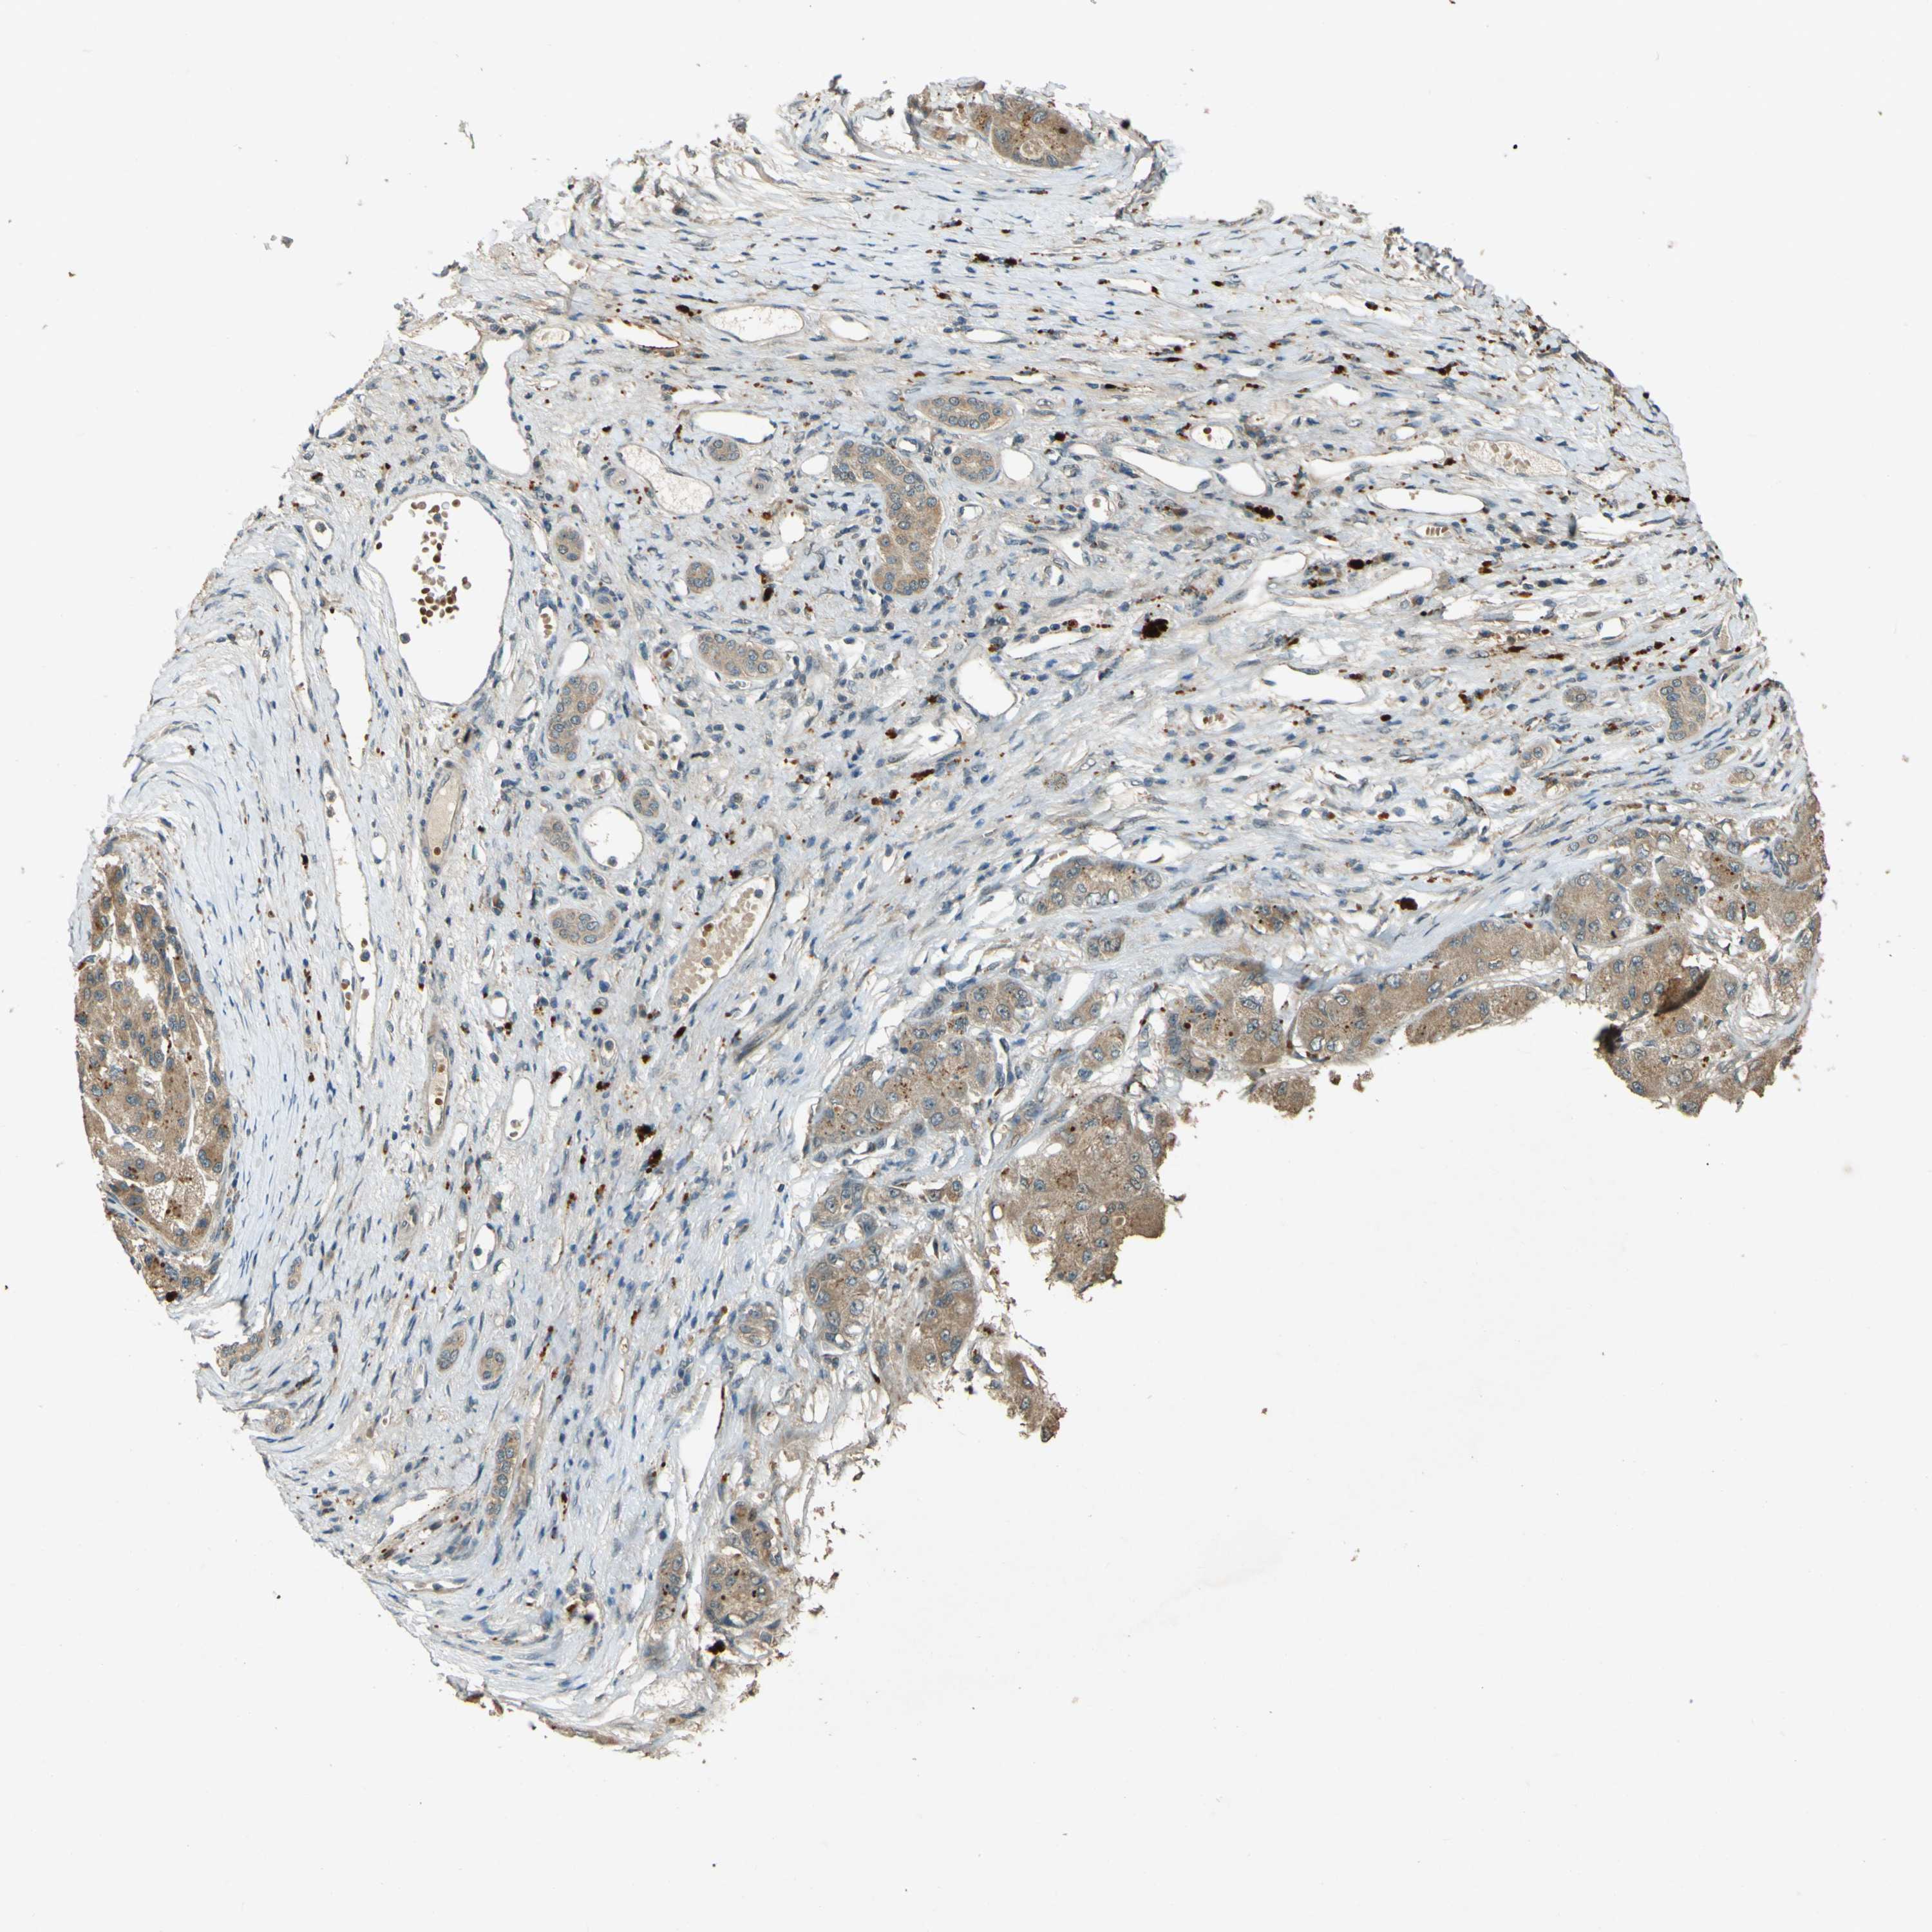

LIVER CANCER - Protein expressioni

A mouse-over function shows sample information and annotation data. Click on an image to view it in a full screen mode. Samples can be filtered based on level of antibody staining by selecting one or several of the following categories: high, medium, low and not detected. The assay and annotation is described here.

Note that samples used for immunohistochemistry by the Human Protein Atlas do not correspond to samples in the TCGA dataset.

Antibody stainingi

Antibody staining in the annotated cell types in the current human tissue is reported as not detected, low, medium, or high, based on conventional immunohistochemistry profiling in selected tissues. This score is based on the combination of the staining intensity and fraction of stained cells.

Each image is clickable and will lead to virtual microscopy that enables deeper exploration of all samples and also displays staining intensity scores, fraction scores and subcellular localization as well as patient and tissue information for each sample.

Antibody HPA020255

Antibody HPA026686

Antibody CAB013512

Staining

High

Medium

Low

Not detected

Intensity

Strong

Moderate

Weak

Negative

Quantity

>75%

75%-25%

<25%

None

Location

Nuclear

Cytoplasmic/membranous

Cytoplasmic/membranous,nuclear

Cholangiocarcinoma

Carcinoma, Hepatocellular, NOS